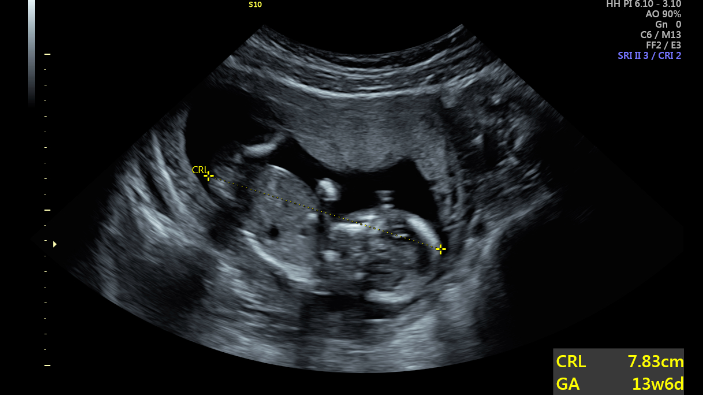

It was the ultrasound that changed things. When she heard the heartbeat, “I heard life. I even heard something divine,” Jasmine shared. “This is not something to get rid of; it’s very real.” It was then Jasmine knew she could not abort. She was eager to return to the Pregnancy Center.